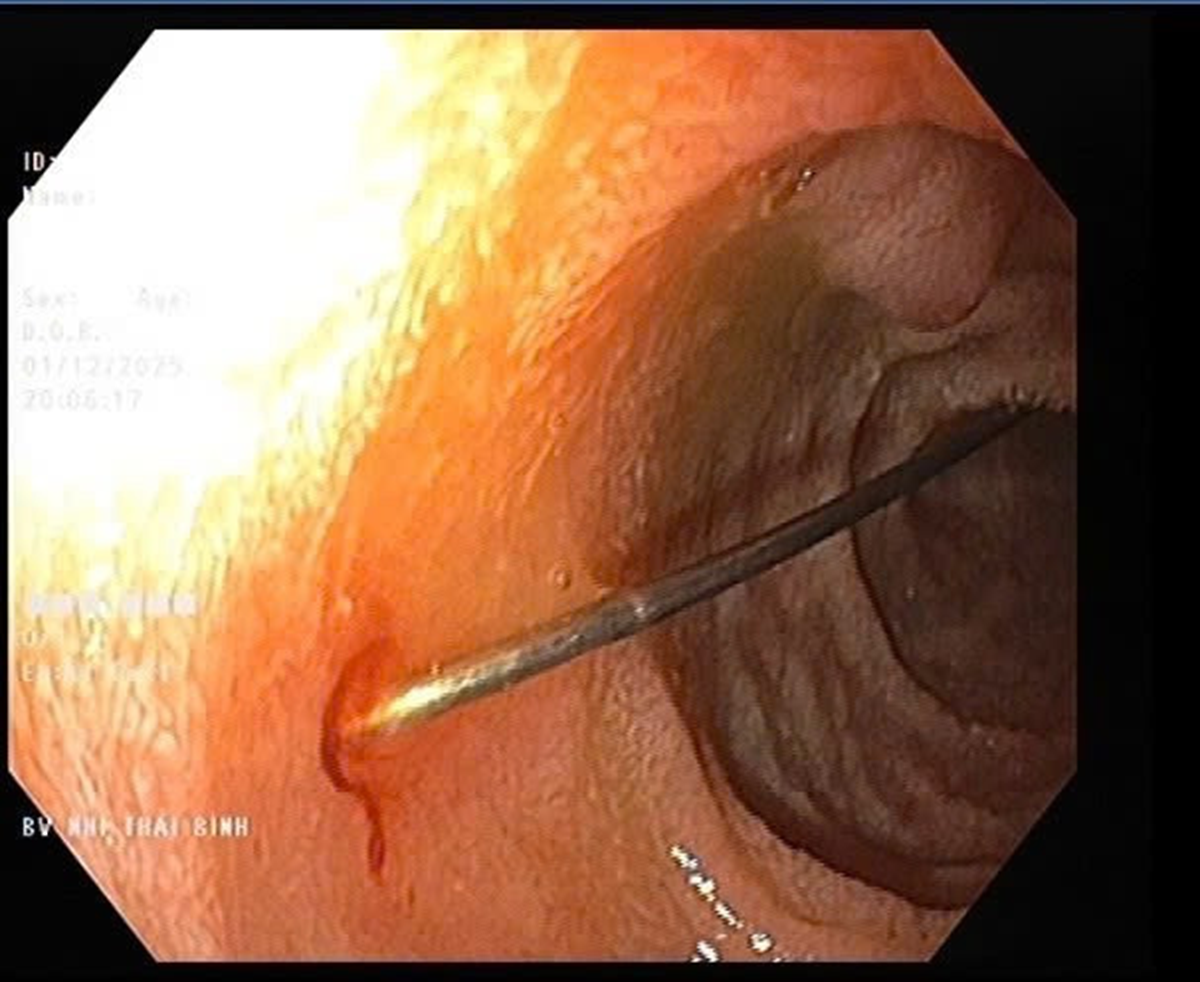

Sau khi thăm khám, trẻ được chẩn đoán dị vật đường tiêu hóa và chỉ định nhập viện vào Khoa Tiêu hóa để theo dõi, hội chẩn và xử trí cấp cứu. Hình ảnh nội soi quan sát thấy niêm mạc thực quản và dạ dày của trẻ không viêm loét; tại hành tá tràng D1-D2 phát hiện dị vật kim may dài 4cm, một đầu nhọn cắm vào thành tá tràng, một đầu nhựa tròn hình cúc đang nằm trong lòng ruột.

Qua nội soi phát hiện cây kim dài 4cm. Ảnh: Bệnh viện cung cấp.

Bệnh nhân được chỉ định nội soi can thiệp cấp cứu, tránh nguy cơ dị vật di chuyển sâu và gây tổn thương nghiêm trọng.